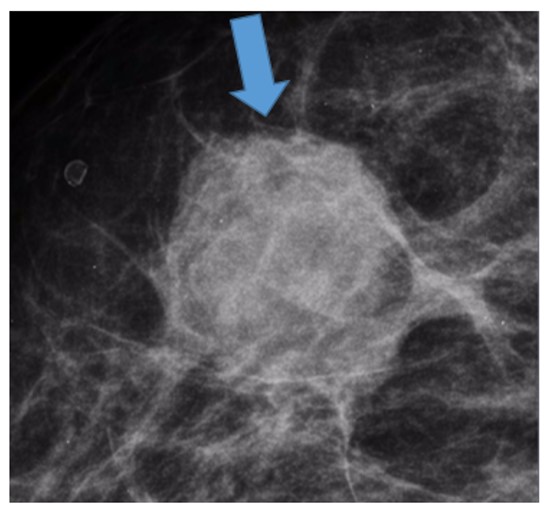

Nódulos na mamografia - descrição e classificação segundo o bi-rads

Prof. Dr. Rodrigo Menezes Jales